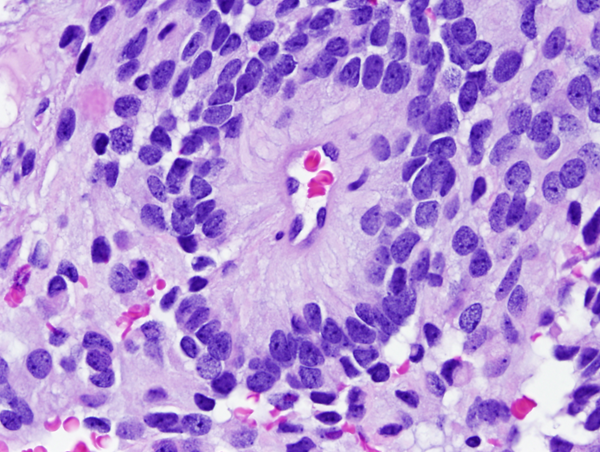

![]() Ependymoma of the 4th ventricle |

Microscopically, the tumor cells resemble normal ependymal cells and are arranged in perivascular pseudorosettes (tumor cell nuclei located at some distance from a central vessel with delicate processes radiating toward the vessel wall), tubular structures like the central canal of the spinal cord, and papillary formations. Ependymoma has distinctive ultrastructural features, including cilia, microvilli, and desmosomes. Ependymomas are graded as grade II or III according to the WHO system. Most are low-grade (WHO grade II). Some have increased cellular density, mitoses, necrosis, and microvascular proliferation while retaining the typical ependymoma tissue pattern (anaplastic ependymoma, WHO grade III).